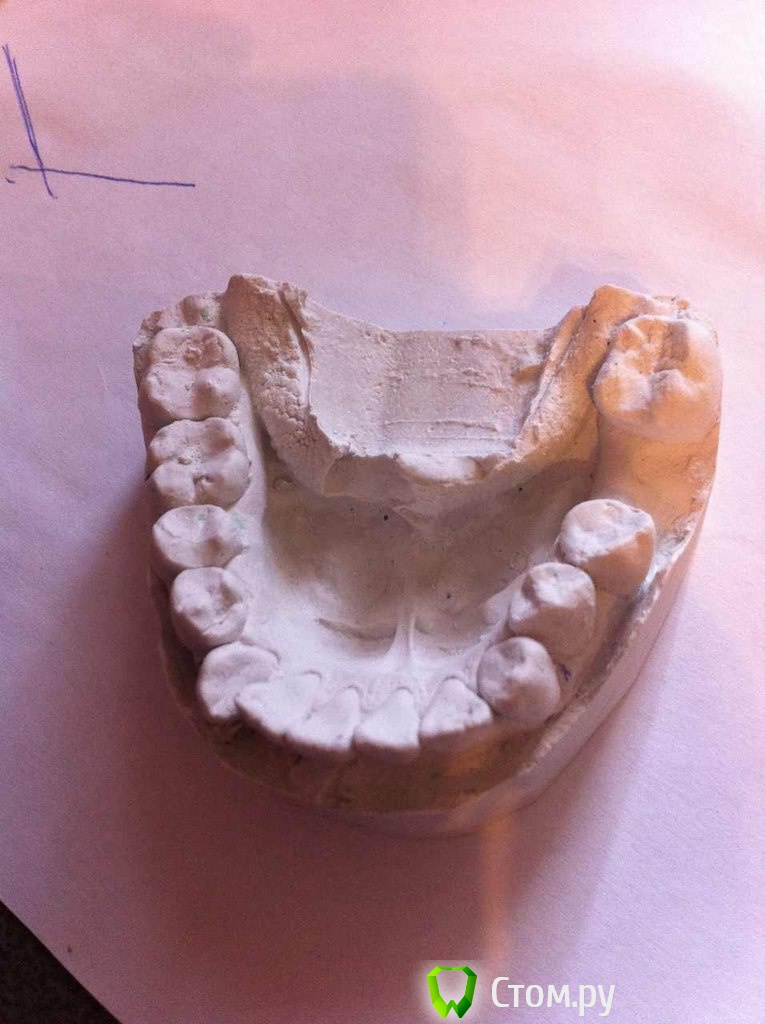

IgorH Опубликовано 7 апреля, 2014 Поделиться Опубликовано 7 апреля, 2014 Добрый деньИнтресует Ваше мнение по поводу необходимости удаления премоляров по моим расчетам-1 скелетный класс,SNA=80SNB=74ANB=6Ось Y=77SN-MP=46вертикальный тип роста WITS меньше 1 мм поэтому 1 скелетный класс по дуге:на вч дефицит места 11 ммна нч 8 ммуглы резцов к плоскостям челюстейвч 115 нч 102 межрецовый угол 107 согласно треугольникам Фастлайта,для первого класса углы 110/90значит нужно сделать навч 115 ретрузию до 110 на нч 102 ретрузию до 90 итого:дефицит места,протрузия,выпуклый профиль,зубы вне дуги Все говорит о том,что необходимо лечение с удалением 4 зубов,интересует Ваше мнение Заранее Благодарю Ссылка на комментарий

IgorH Опубликовано 17 апреля, 2014 Автор Поделиться Опубликовано 17 апреля, 2014 как показывал Попов, на семинаре по вектор тасам, не имеет значение давность удаления... на винтах все заезжает без всяких наклонов...зы: и 36 кстати до сих пор не удален) а вообще много терапии вначале.... 12 с "кистой", 47 нужно проверить, если все как на снимке, то все "плохо", в месте контакта с 48... 2 мм дефицита места дадут +6 к торку во фронте, сепарируете между клыком и четверкой по 0.7, итого 2-1.4=0.6мм это 1.5 градуса к торку- это незаметно, даже для нее...но если смотреть в рот более менее комплексно, и подумать о долгосрочной перспективе то, если оставить замученные 5ки вверху и 6ки внизу, то придется удалять целые 8ки!!! а судя по качеству терапии 5ки и 6ки долго не прослужат... вот поэтому лично я бы снес 5ки верх и 6ки низ... закрывать все с максимальной потерей(возможно даже со стабилизацией фронта на определенном этапе, но это как пойдет) и ставить 8ки нормально...Благодарю Вас за детальный ответ)в моих расчетах на вч дефицит места не 2 мм,а 11 мм,возможно я ошибся,я считал по моделям,мезио-дистальные размеры зубов,и место в зубном ряду с помошью нитки(знаю есть специальные графические методы) .а как Вы просчитываете деффецит места в зубном ряду? максимальная потеря,вы имеете ввиду анкораж?я планирую на вч устанавливать Даемон с высоким торком,для стабилизации фронта Ссылка на комментарий

LeFor Опубликовано 17 апреля, 2014 Поделиться Опубликовано 17 апреля, 2014 в моих расчетах на вч дефицит места не 2 мм,а 11 мм,возможно я ошибся,я считал по моделям,мезио-дистальные размеры зубов,и место в зубном ряду с помошью нитки(знаю есть специальные графические методы) .а как Вы просчитываете деффецит места в зубном ряду? на глаз)) у меня же есть только фото... дефицит ну максимум 4мм... максимальная потеря,вы имеете ввиду анкораж? анкораж, на сколько я знаю переводится примерно как- опора... так что я имею ввиду наоборот, закрывать пространства с максимальной потерей опоры. я планирую на вч устанавливать Даемон с высоким торком,для стабилизации фронта или я ничего не понял, или... зачем высокий торк если вы боитесь протрузии? Мне ближе всего лечение с удалением вверху 5,и внизу 46,правда,я еще выбираю,убирать 46 или 45, в любом случае,оставшийся зуб планируем перелечивать,и качественно запломбировать канал только проверьте прежде 47... если там все обойдется, то лучше убрать 46, т.к. 45 лучше выглядит+ больше вероятности что его нормально пролечат+ симметричное лечение предсказуемее.. 1 Ссылка на комментарий